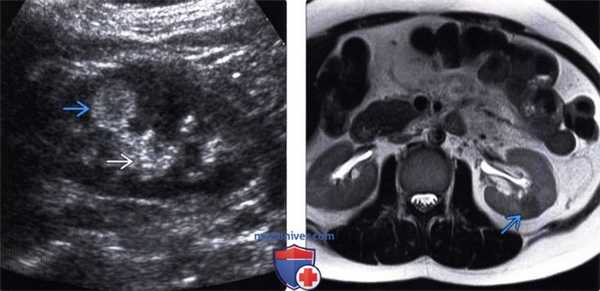

(Слева) УЗИ в сагиттальной плоскости: эхогенное образование верхнего полюса почки с признаками, характерными для ангиомиолипомы (АМЛ).

(Справа) КТ, постконтрастное изображение, аксиальная проекция: визуализировано образование жировой плотности в правом верхнем полюсе левой почки, которое соответствует эхогенному образованию, выявленному на предшествующем УЗИ. Такие признаки характерны для ангиомиолипомы (АМЛ). (Слева) КТ без контрастирования и с контрастированием, аксиальная проекция: слабовыраженные участки жира во множественных АМЛ правой почки. Обратите внимание на наличие простой кисты в левой почке.

(Левый) На продольном УЗ срезе левой почки визуализируется гиперэхогенное новообразование без затенения. Образование менее эхогенное, чем окружающая клетчатка почечной пазухи. Внешний вид неспецифичен, однако основными причинами являются АМЛ и ПКР. Требуется дообследование (КТ или МРТ).

(Правый) На аксиальном Т2 HASTE МР изображении без жироподавления у этого же пациента визуализируется низкоинтенсивный сигнал от опухоли. При частичной нефрэктомии подтвердился диагноз маложировой ангиомиолипомой (АМЛ).